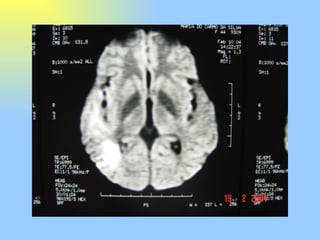

Este documento descreve o caso de uma paciente de 43 anos que apresentava fortes dores de cabeça do lado direito, náuseas, vômitos e sensibilidade à luz e ao som, diagnosticadas como enxaqueca em salvas. Exames de imagem revelaram um aneurisma gigante na artéria cerebral média direita, e depois a paciente desenvolveu fraqueza parcial do lado esquerdo do corpo devido a um coágulo sanguíneo.